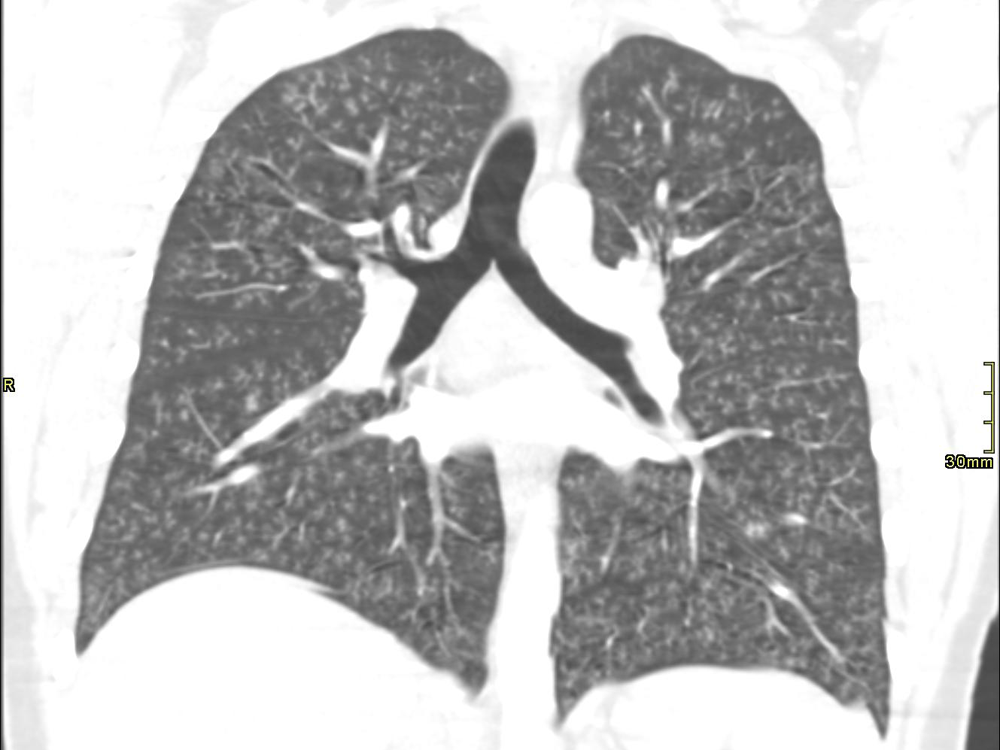

this chest x-ray of a 17-year-old ontario boy was taken two days after he was hospitalized with a vaping-related lung injury. canadian medical association journal

a 17-year-old canadian teen who narrowly escaped needing a double lung transplant to save his life is believed to have developed the first suspected case of “popcorn lung” associated with vaping.despite its name, there is nothing trivial about it. the case represents a potentially fatal lung injury experts had long suspected vape products were capable of causing, and it comes as the number of teens vaping and the number of vaping-related illnesses are on the rise in both canada and the united states.in a report fast-tracked by canada’s top medical journal, doctors describe how the previously healthy london, ont. high-school student spent 47 days in hospital, much of it on aggressive life support, including tethered to a machine used to rescue dying people during the sars outbreak of 2003.london health officials first revealed the case — now believed the first, or “index case” of vaping-related lung injury in canada — in september, but only now have details been published.the boy had vaped daily for five months, alternating between different flavoured cartridges and regularly adding thc to his vaping fluid, when he developed a sudden fever and severe cough.“he got very sick, very quickly,” said dr. karen bosma, an intensivist at london health sciences centre and lead author of the report published thursday in the canadian medical association journal.the unidentified youth arrived in the emergency department of his local hospital one week after his symptoms began. he was diagnosed with pneumonia and sent home with a prescription for antibiotics.five days later, he was back at hospital with worsening “dyspnea” — air hunger. he was struggling to get air into his lungs. x-rays and a ct scan of his chest showed a phenomenon known as the “tree-in-bud” pattern.the main airways in the lungs branch like a tree. the further you go the more numerous the airways.his medical team believe he developed bronchiolitis obliterans, an inflammation of the thin-walled, tiny airways called bronchioles that go to the furthest parts of the lung. normally the tubes are filled with air, and air appears black on a ct scan. but when they become inflamed, the airways become impacted with inflammatory cells that appear white on a ct scan. “they look like, literally, a tree with branches with tiny buds on the ends of them,” bosma said.